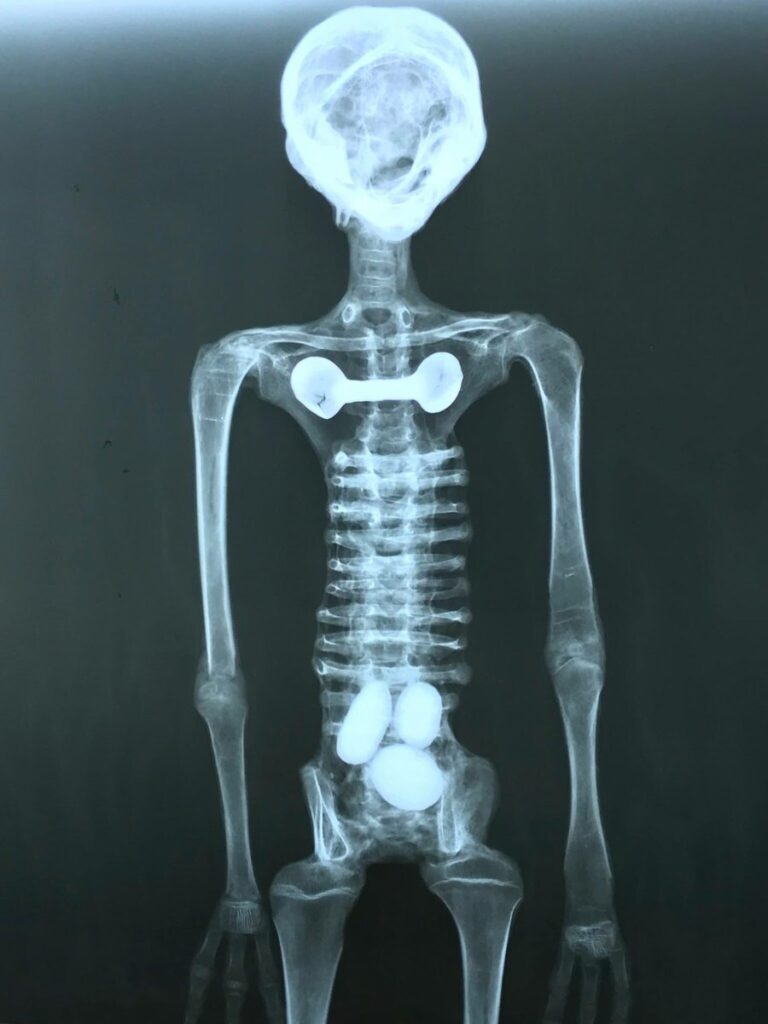

Dalla TAC in una mano hanno trovato un impianto, non ortopedico, ma tecnologico, in un’altra mummia ne è stato trovato uno appena sotto quelle che potrebbero essere le nostre clavicole.

Una femmina aveva tre uova in zona pelvica.

La mano non ha il palmo, solo tre dita con cinque falangi che consentono “avvolgimenti” al posto di un uso tipo “pinza” (il relatore parla di evoluzione rispetto alla nostra mano).

Il femore non ha un attacco sferico ma discoidale tale da vincolare il movimento ed ho l’impressione che sia funzionale al mantenimento di un equilibrio dinamico avendo la testa una massa rilevante rispetto al corpo.

Anche i piedi hanno solo tre dita con più falangi e senza la “pianta del piede”, quindi, possono camminare su superfici non uniformi mentre il nostro piede cerca sempre superfici piane.